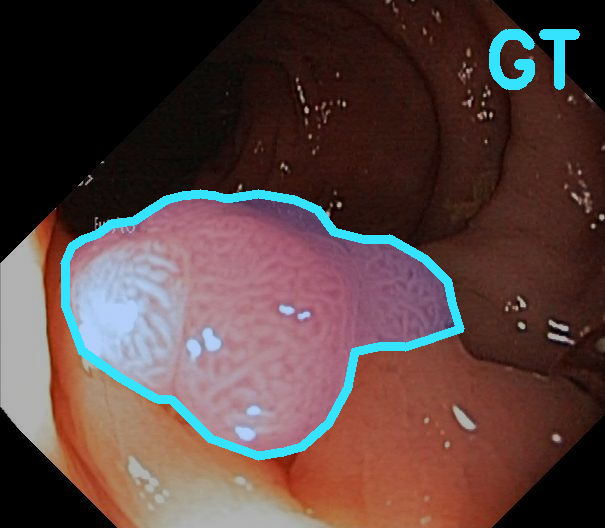

TransFuse is evaluated on both 2D and 3D datasets to demonstrate the effectiveness. As different medical image segmentation tasks serve different diagnosis or operative purposes, we follow the commonly used evaluation metrics for each of the segmentation tasks to quantitatively analyze the results. Selected visualization results of TransFuse-S are shown in Fig. 2.

Results of Polyp Segmentation. We first evaluate the performance of our proposed method on polyp segmentation against a variety of SOTA methods, in terms of mean Dice (mDice) and mean Intersection-Over-Union (mIoU). As in Tab. 3, our TransFuse-S/L outperform CNN-based SOTA methods by a large margin. Specifically, TransFuse-S achieves 5.2% average mDice improvement on the unseen datasets (ColonDB, EndoSene and ETIS). Comparing to other transformer-based methods, TransFuse-L* also shows superior learning ability on Kvasir and ClinicDB, observing an increase of 1.3% in mIoU compared to TransUnet. Besides, the efficiency in terms of the number of parameters as well as inference speed is evaluated on an RTX2080Ti with Xeon(R) Gold 5218 CPU. Comparing to prior CNN-based arts, TransFuse-S achieves the best performance while using only 26.3M parameters, about 20% reduction with respect to HarDNet-MSEG (33.3M) and PraNet (32.5M). Moreover, TransFuse-S is able to run at 98.7 FPS, much faster than HarDNet-MSEG (85.3 FPS) and PraNet (63.4 FPS), thanks to our proposed parallel-in-branch design. Similarly, TransFuse-L* not only achieves the best results compared to other Transformer-based methods, but also runs at 45.3 FPS, about 12% faster than TransUnet.